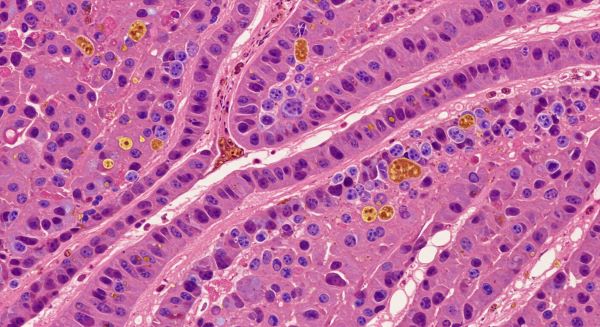

- 간 조직 생검: 필요 시 정밀 진단